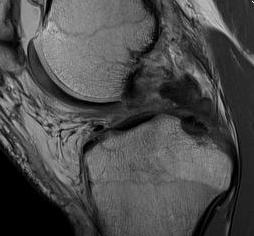

Posterior subluxation of tibia

Grade 3 PCL disruption - posterior tibia subluxed behind posterior aspect femoral condyles

MRI

PCL completely torn

PCL midsubstance tear with lengthening

PCL tibial avulsion

PCL femoral avulsion